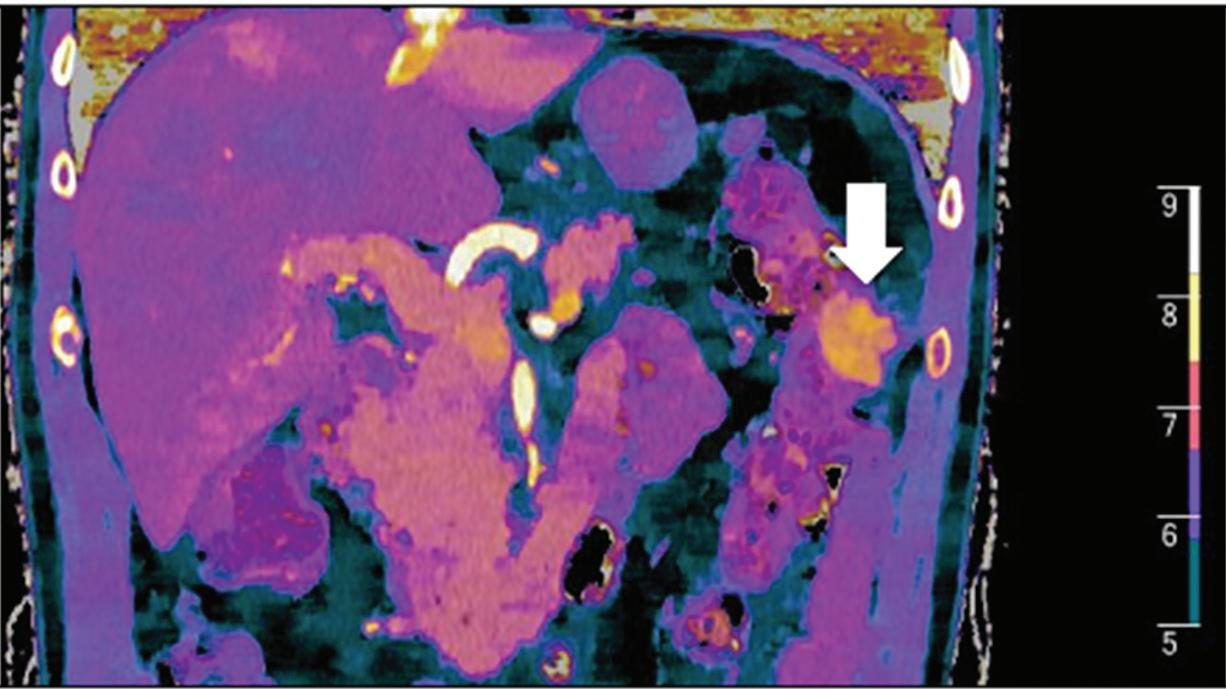

Renal and adrenal gland tumors. Contrast-enhanced-DECT images are particularly useful for the characterization of incidental renal or supra-renal lesions and for their follow-up, without the need of conventional unenhanced acquisition, translating into achieving a 30% mean dose savings for triphasic and up to 50% for biphasic renal protocols in daily clinical practice.17 It is also very useful in depicting hypervascular renal cell carcinoma metastasis in the liver or other sites, such as in the peritoneum and bowel wall (Figures 2 and 3).

Z effective

Spectral CT is able to generate Z effective images that show the mean atomic number of the material present in a voxel (Z effective values) and can be displayed as color coded overlay maps. Z effective images may be helpful to enhance the visual differences between different tissue types.46 Furthermore, due to the high atomic number of iodine compared to other tissues present in the human body, the Z effective images can highlight enhancing structures (Figures 2, 3, 4, and 5) and could be used for quantitative analysis to differentiate benign from malignant tumors or lymph nodes.16,45,47

Effectiveness of spectral CT imaging for detection of hypervascular liver metastases. A small hypervascular metastasis (arrow) from renal cell carcinoma. (a) Axial contrast-enhanced conventional CT image obtained in the arterial phase, corresponding (b) monoenergetic 50 keV, and (c) Z effective image.

Effectiveness of spectral CT imaging for detection of a peritoneal implant from a renal cell carcinoma invading the bowel wall (arrow). (a) Coronal contrast-enhanced conventional CT image obtained in the arterial phase, corresponding (b) Z effective, (c) monoenergetic 50 keV, and (d) iodine-density image.